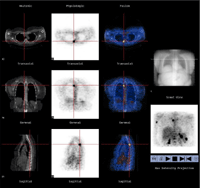

GE Medical Systems (Milwaukee, WI) and Elgems Ltd (Haifa, Israel) have developed a dual-modality imaging system ("Millenium VH" or "Hawkeye") that combines SPECT and CT, similar to the approach developed at UCSF. The system performs planar scintigraphy or SPECT, and also performs coincidence detection of annihilation photons for imaging 18F-fluorodeoxyglucose (FDG) and other positron- emitting radionuclides, and incorporates a low-resolution CT scanner for anatomical localization and attenuation correction of the radionuclide data. The Hawkeye system now is installed in the Nuclear Medicine Clinic at Moffitt Long Hospital (Figure 2). It is interfaced both into the Radiology PACS system and into the Nuclear Medicine local area network. This makes it possible to view images from the Hawkeye directly on the GE Integra workstation next to the camera, or on an additional Integra workstation in the Nuclear Medicine view room, and also on PACS terminals and on the Nuclear Medicine Pegasys (Philips ADAC) workstations. The system is used for both clinical and research studies. It has been used for routine clinical procedures (Figure 3) such as bone, renal and cardiac studies as well as for selected FDG coincidence imaging procedures. Single slice CT images having a slice width of 10 mm can also be acquired with the unit, and it is expected that in the future most nuclear medicine clinical studies will benefit from this level of co-registered CT acquired with nuclear medicine image sets. Areas of particular relevance of CT to clinical interpretation of nuclear medicine images include bone and whole body imaging. A very promising capability of the technology is the improved attenuation correction in cardiac imaging. Because of the improved signal quantification the unit produces through more accurate attenuation correction and image segmentation approaches, it will be of particular value in new research protocols such as new radioimmunotherapy approaches being developed together with investigators in Medical Oncology and Pediatric Oncology at UCSF. This promises to make in vivo dosimetry with nuclear medicine radiopharmaceuticals much more accurate than with more traditional methods. |

Figure 2: A GE Millenium VH ("Hawkeye") SPECT/CT system recently was installed in the Nuclear Medicine Program within the Department of Radiology at UCSF. This system combines SPECT, coincidence imaging of FDG, and low-resolution CT in a single integrated system, and now is used for clinical imaging at UCSF.

Figure 3: GE Millenium VH (see Figure 2) produces images that allow correlation of functional information from SPECT or FDG with anatomical information from CT. Illustrated above are images from a patient with metastatic melanoma. There is a focus of increased FDG (F-18 fluorodeoxyglucose) uptake in pedicle of T4 consistent with metastatic focus. Normally, the Hawkeye system is used to image single photon emitting radiopharmaceuticals, but the unit installed at UCSF has a thick crystal and coincidence circuitry, making it possible to image FDG and other positron emitting compounds as shown here. Images shown are CT on left ("Anatomic"), FDG in next row ("Physiologic"), and fused (combined) CT and FDG images in the next row, with a scout CT image on the right. A three-dimensional FDG projection image (lower right) shows additional metastases in the right humerus and multiple metastases in the spleen.